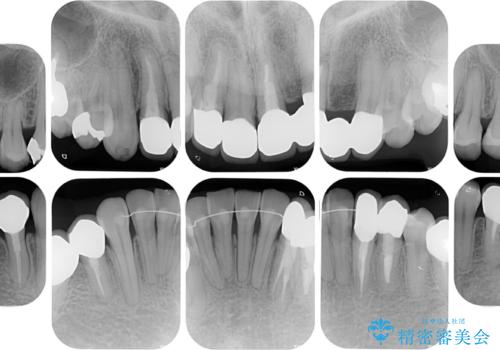

- 非対称な前歯や奥歯の目立つ銀歯を気にして来院された患者様です。

左上前から2番目の歯は、以前裏側に位置していたことから抜歯をされていましたが、前歯の非対称が長年気になっているとのことでした。

矯正治療によって前歯にスペースを作り、左右対称となるようにオールセラミッククラウンにて補綴治療を行うとしました。

他にも奥歯の咬み合わせに問題があったので、全顎的な矯正治療を行い、前歯以外にも口を開けたときに目立つ奥の銀歯をセラミッククラウンにて補綴治療を行うこととしました。

前歯の横幅が大きいことも気になっていたので、矯正治療で前歯5本の幅をコントロールしながら移動させ、治療開始前より一回りサイズの小さいセラミッククラウンを装着することができました。